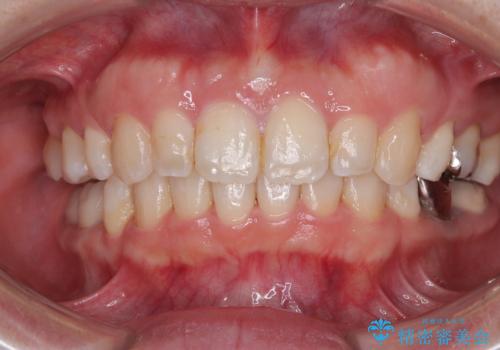

前歯と奥歯のガタガタを矯正で改善

担当医 河口智英